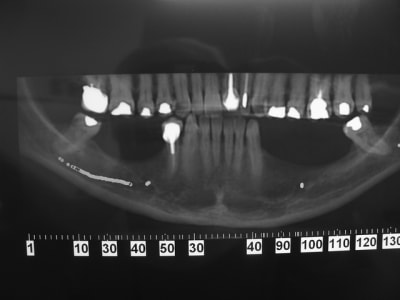

Patiente agée d'une trentaine d'année. En bouche la crête osseuse est inapparente et absence de gencive attachée.

La patiente n'envisage que du fixe et attend un résultat "esthétique.

Dans les secteur d'emmergence du nerf mandibulaire la palpation est douloureuse.

pano_origine_nwhu2w.jpg

sinon secteur 3 y a peut être moyen dans certaines zones de travailler avec l'expansion...mais pas facile comme cas...surtout si la demande esthétique est +++

1. 2 séances d ostéotension

2. Epaississement vestibulaire en zone molaire nanobone prfd jason

3. pose de 2 cylindres enfouis en 34 44

4. pose de monodisk en 36 37 46 47 enfouis bloqués par vis ostéosynthèse

Mouais! Mais elle veut la hauteur en plus.

Justement c'est la laxité du lambeau qui m'inquiète +++++

Pour le gain en hauteur, il n'y a que la greffe autogène qui donne de bon résultats, avec des bloc allogenique ???

En basale, il n'y aura pas de gain en hauteur, mais elle aura des dents, certe longues mais fonctionnelles.

En classique, il faudra faire un mix savant entre expansion greffe ROG.... C'est pas gagné

Bien vu! Je ne connaissais pas. C'est le même cas. J'aurai bien tenté mais ce qui "m'inquiète", c'est l'emmergence du mandibulaire. Sur le modèle du site je ne le vois pas; sur mon cas il serait juste au niveau du premier bloc et je me pose la question du surplomb ou de "l'irritation" possible.

et virer les dent qu'il reste pour implanter à la place et faire un transvissé classique sur 5/6 implant entre les mentonniers?

bon d'accord, on sacrifie des dents intactes, mais versus des greffes d'apposition dans les secteurs mandibulaires, on peut se poser la question...

Nous avons traité un cas comme ça avec D57,(secteur 3) os D1, manque de largeur résultat (de mémoire je n'ai pas les photos ici) 2 implants en même temps que l'expansion (34/37) et la suite 3 mois après le déplacement des volets vestibulaires, (bloqués sans vis) mais protégés par un bridge provisoire.

En conclusion, ce n'est pas un cas ou je ferais une greffe même pré ajustée (résultats en Décembre Pluton), mais une expansion sans doute avec déplacement/fracture du volet vestibulaire car os D1, mais si ça ce passe bien simple bone splitting et pose des implants dans la séance.